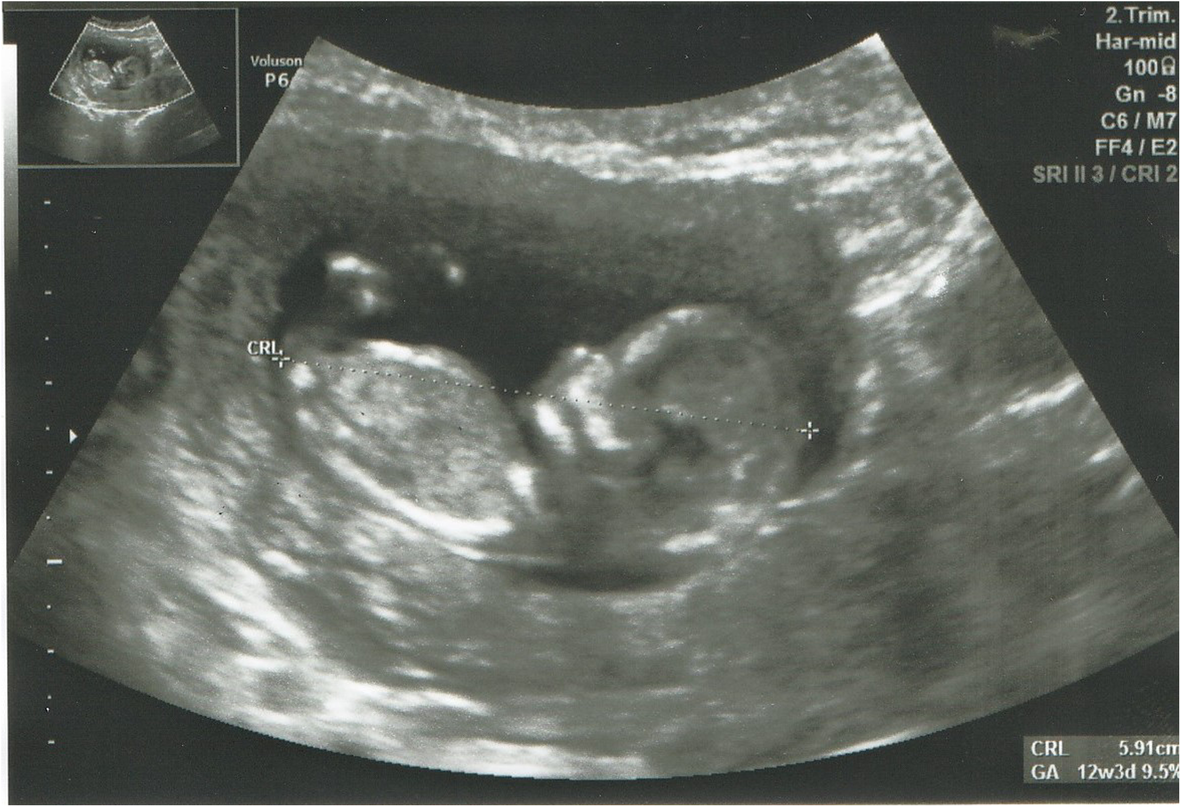

Fig. 1From: Severe haemophilia a in a preterm girl with turner syndrome - a case report from the prenatal period to early infancy (part I)Fetus profile in 12th week of pregnancy (NT- 1.2 mm and CRL at 5.9 mm). (written consent to publish was obtained from the patient’s parents)Back to article page